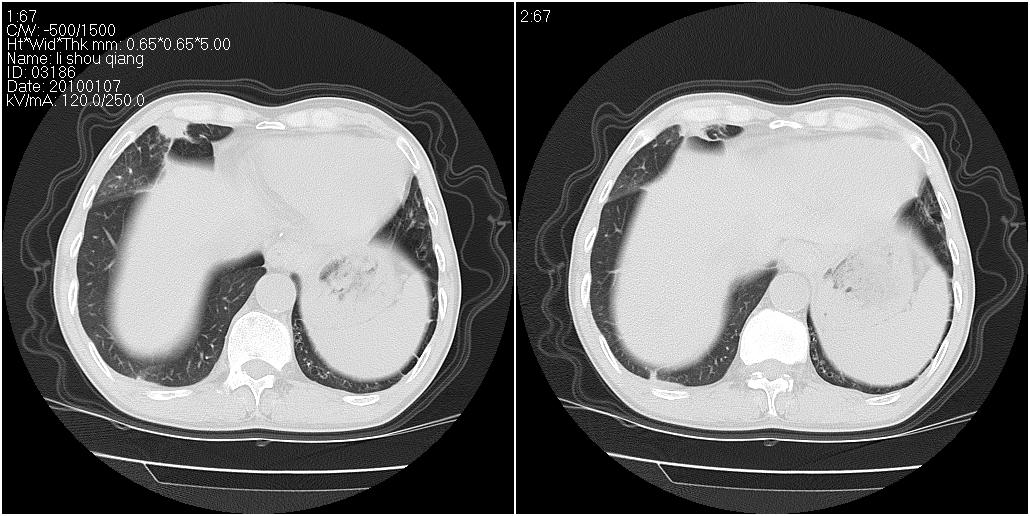

标题: CT24038:男性,58岁。主因咳嗽带血性CT检查。 [打印本页]

标题: CT24038:男性,58岁。主因咳嗽带血性CT检查。

右肺中叶外侧段可见团块影,外形不规则,内见空泡征。左下肺见蜂窝状低密度透亮影,部分层面主动脉旁瘤样突出。考虑右肺中叶外围型肺癌可能性大,左下肺支气管扩张,主动脉弓瘤样突出。

考虑右肺癌可能性大,左下肺支气管扩张,主动脉弓瘤样突出?建议增强

1、右肺中叶病灶内不规则气体影、低密度影,且与胸膜接触面宽,病灶边缘模糊。考虑右肺中叶感染并有脓肿形成。建议抗炎治疗后复查。2、左下叶支气管扩张症。